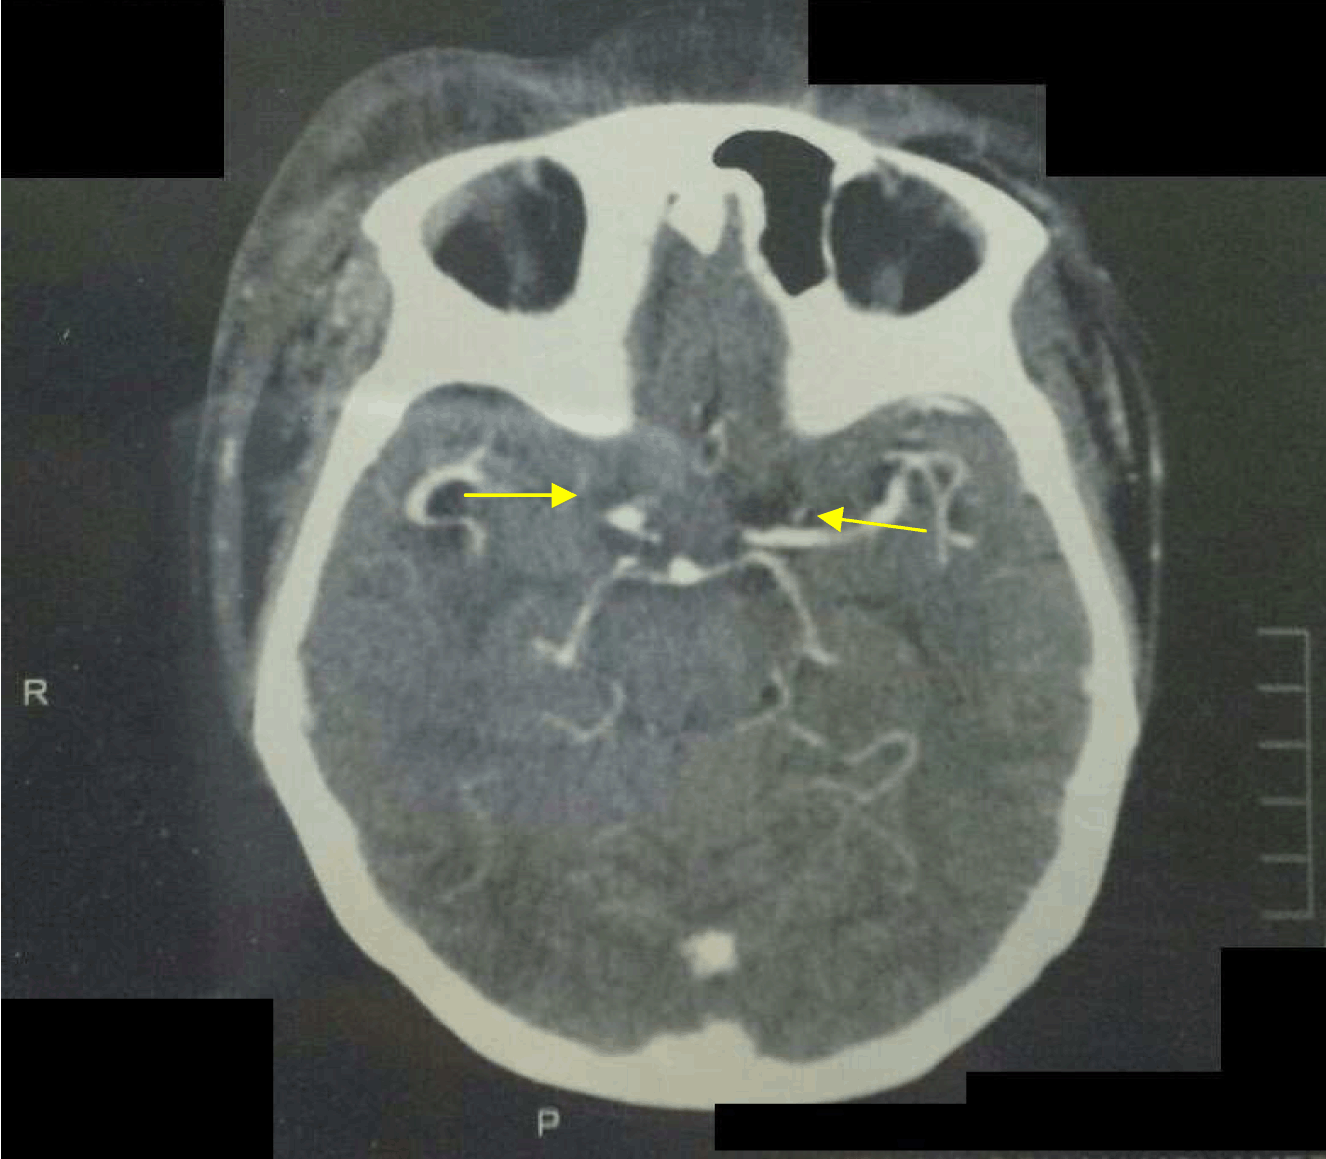

With the source of infection being the mycotic AVF pseudoaneurysm, the initial step of management included aneurysmectomy and AVF ligation to control the systemic infection. Postoperatively intravenous antibiotics and analgesia were administered. The fever subsequently subsided. Next, computed tomography angiogram of the head and neck showed a long segment occlusion on the left internal jugular vein extending to left brachiocephalic and subclavian veins (Figure 4) and evidence of a cavernous sinus thrombus (Figure 5); a diagnosis of a septic cavernous sinus thrombosis was made. The treatment included anticoagulant therapy, IV 3rd generation cephalosporin and periorbital eye dressing with honey and water. After the periorbital swelling and local infection subsided, she was discharged on oral anticoagulant therapy and daily eye dressing. She was later booked for debridement of a necrotic skin infection just below the right eye (Figure 6). After complete resolution of her condition, she now presents with ectropion of the right lower eye lid.

Figure 5: Bilateral cavernous sinus lesions shown on computed tomography scan of brain.